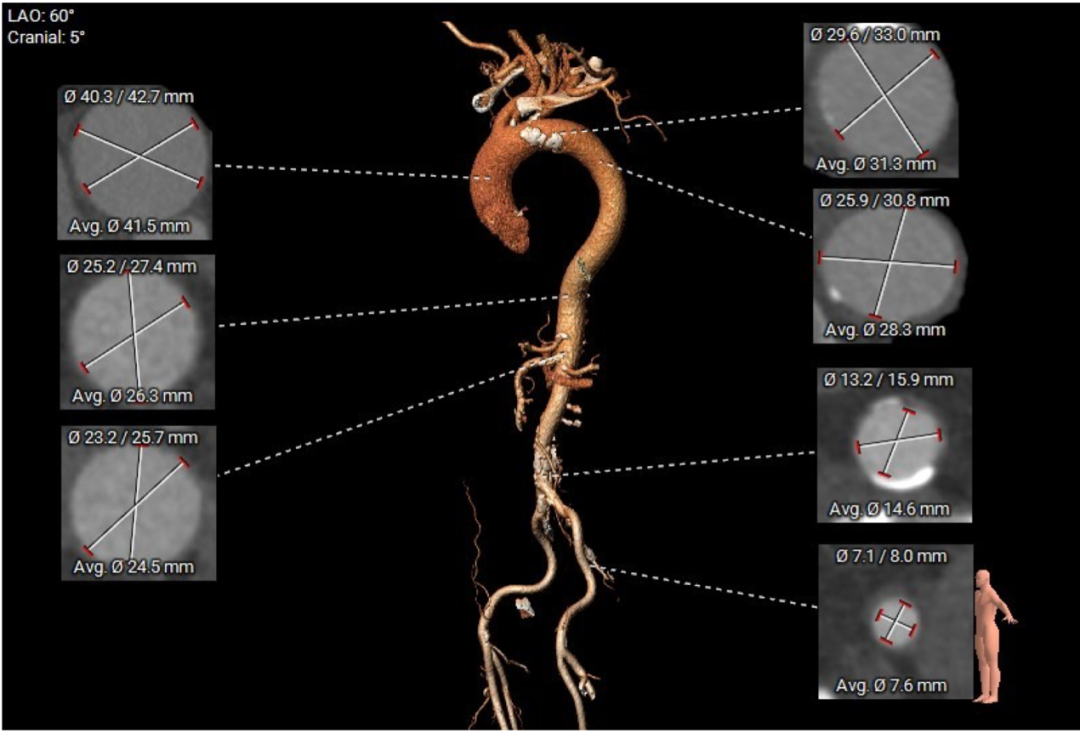

患者主动脉瓣三叶式,瓣叶基本等大,瓣叶稍厚,右无冠瓣瓣叶游离缘轻度钙化,瓣叶交界钙化有融合;主动脉瓣环周长折算直径约29.0mm:

双侧冠脉开口高度可,LCA 11.5mm, RCA 18.7mm;右冠、左冠及分支轻度钙化:

术中建议造影角度LAO 4°,CAU 6°(其它考角度如下图):

横位心,心室角度68°:

主动脉弓、腹主动脉及双侧髂总动脉见多发钙化: